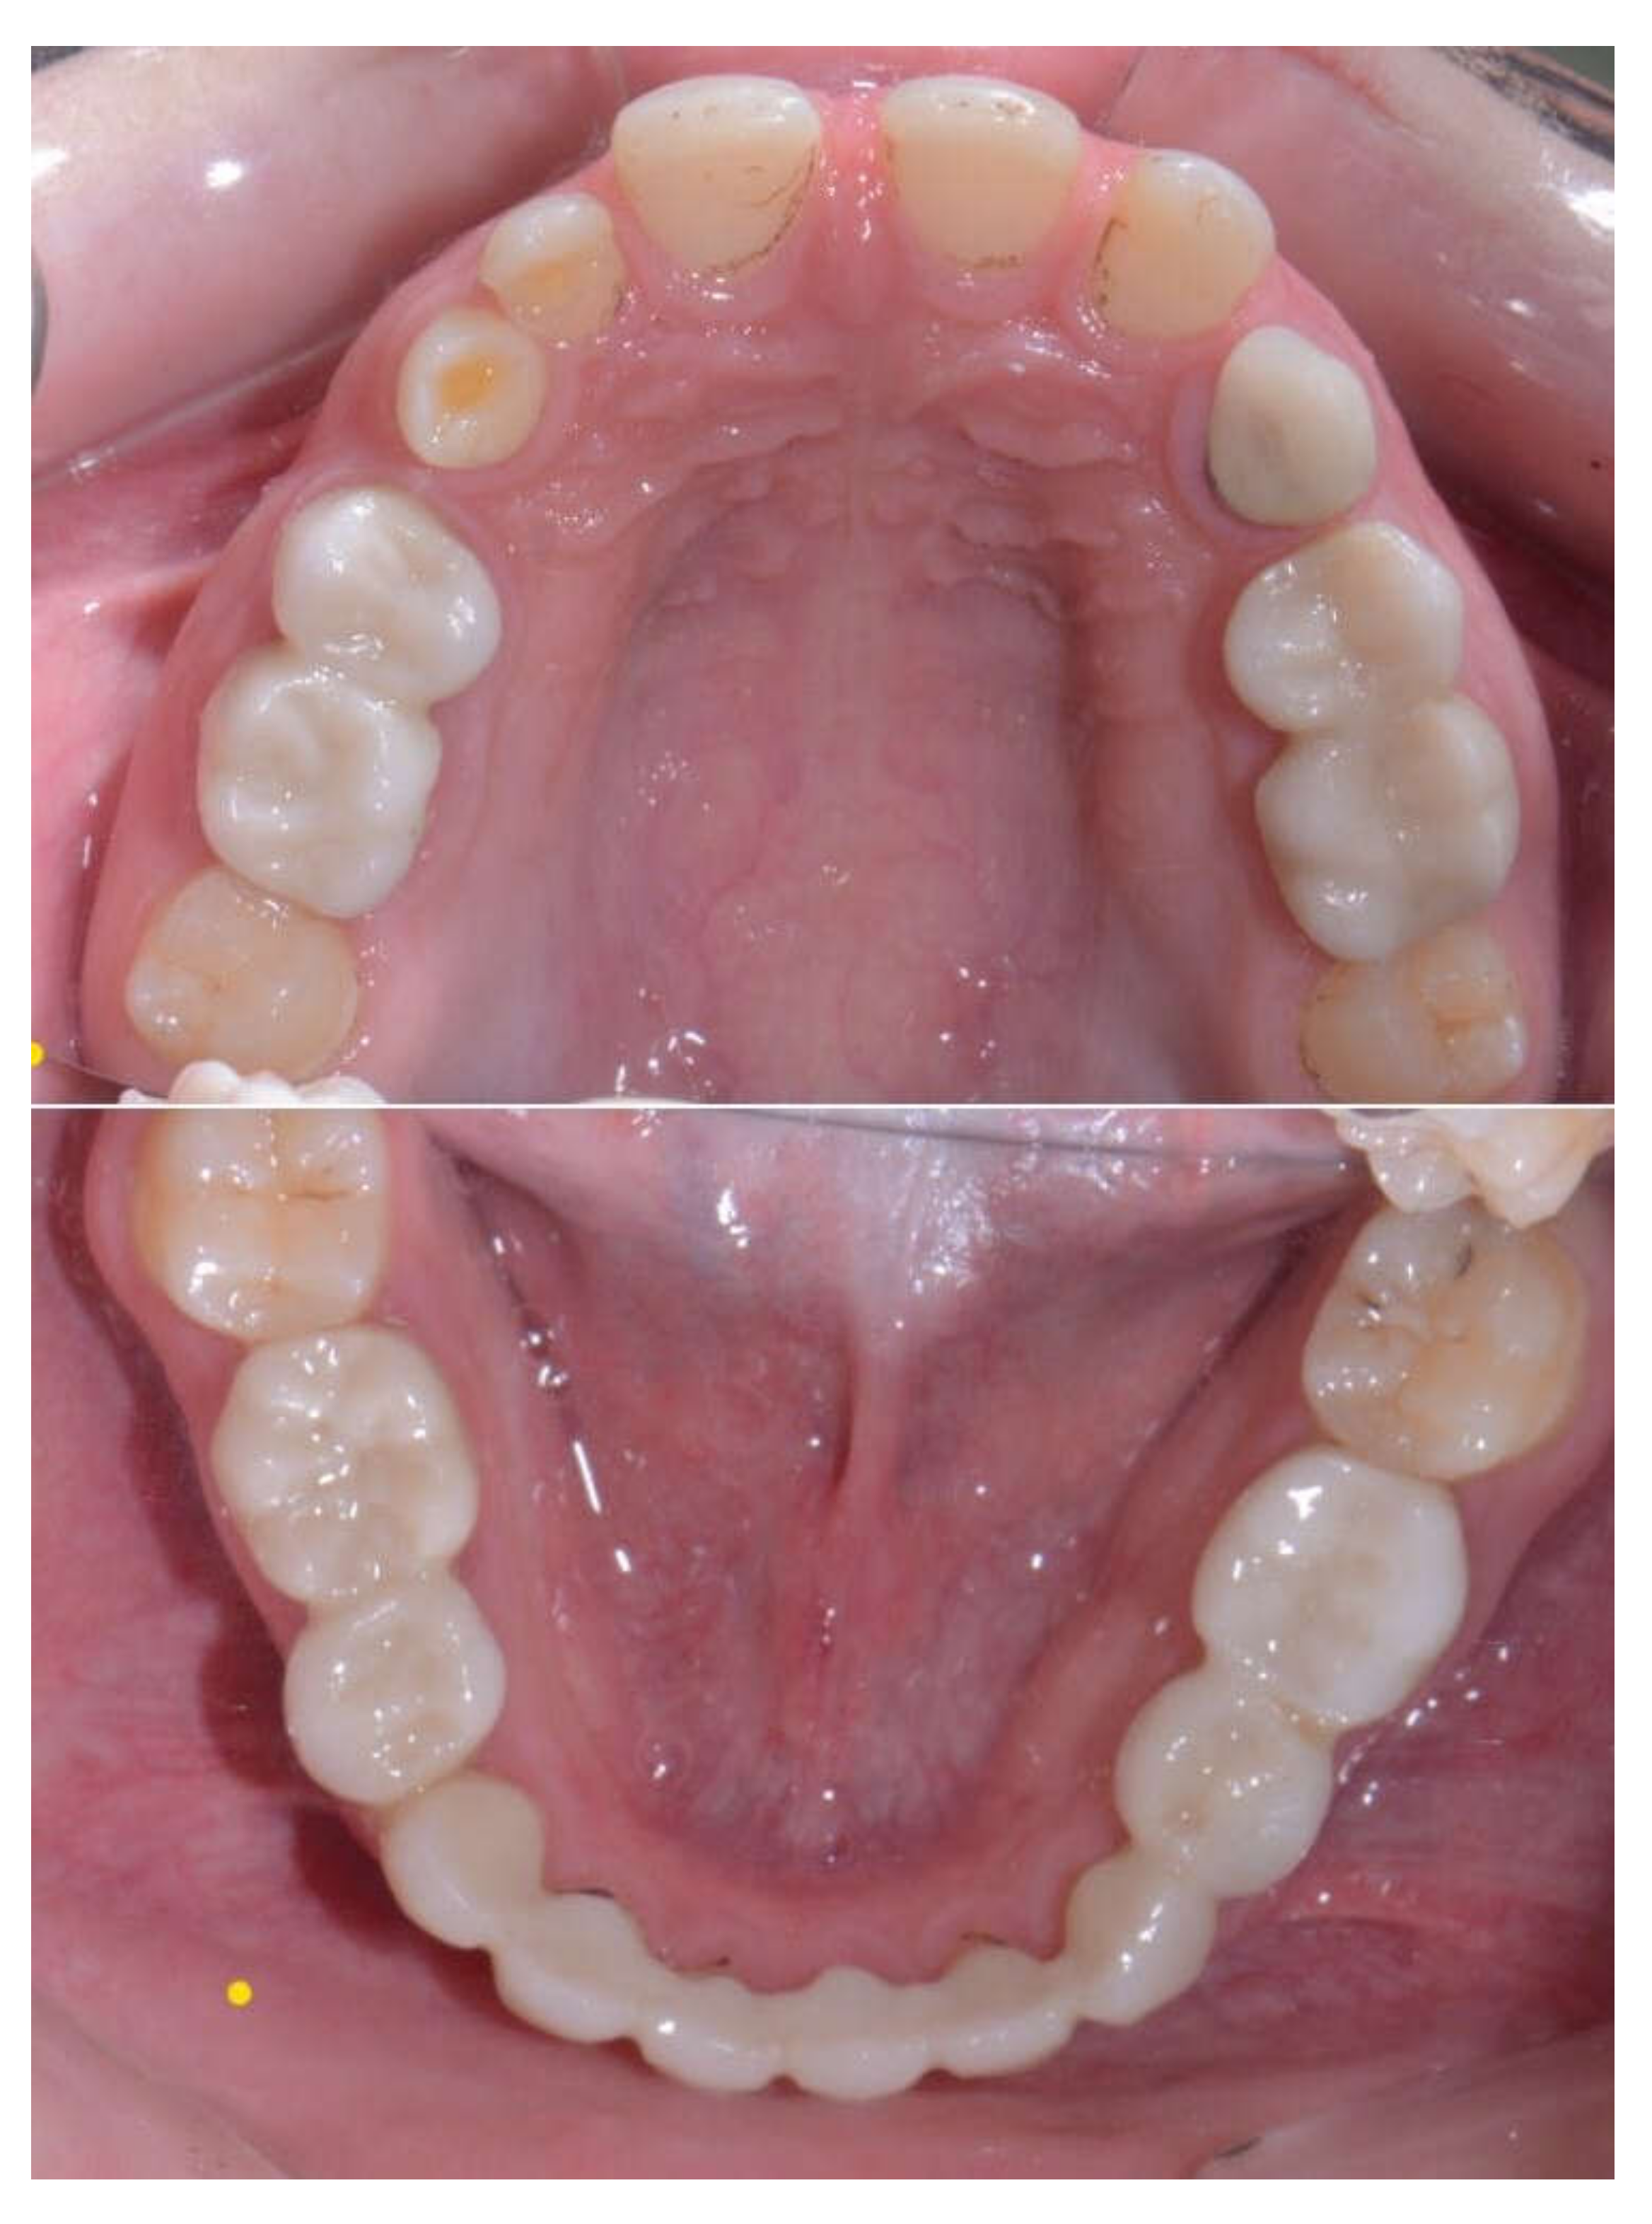

Primary Teeth Supported Fixed Prosthesis—A Predictable Treatment Alternative

2. Materials and Methods

3. Results